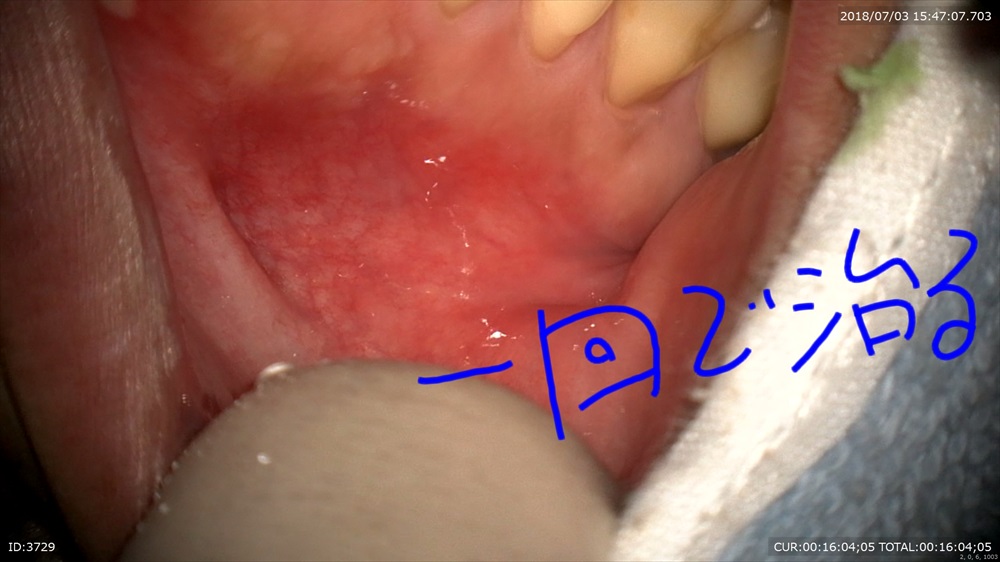

本日↓

腫れと膿が消えました!!

1回で治り根管充填

無痛で1回で終わるのが理想です!!